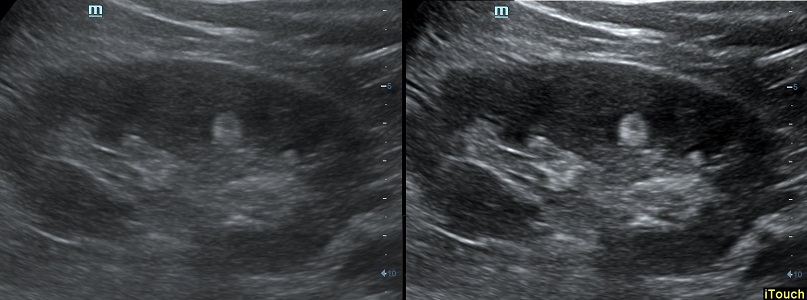

Оптимизация изображения происходит и за счет постобработки. Наиболее часто используемый инструмент - общее усиление (Gain). Усиление делает изображение «ярче», но чем сильнее усиление, тем меньше различия между структурами. Также используются усиление по времени (TGC) и усиление по длине (LGC), которые позволяют изменять отображение на экране послойно, позволяя подсветить гипоэхогенные участки, или, наоборот, снизить визуально эхогенность слишком ярких моментов. Данный вид оптимизации требует много времени, для упрощения работы доктора на приборах Mindray внедрена система автоматической оптимизации - iTouch.